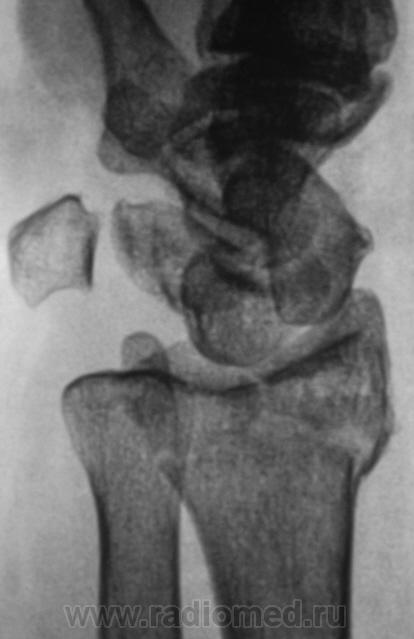

Травма.   Пациент направлен на рентгенографию лучезапястного сустава.

СЛУЧАЙ № 2.